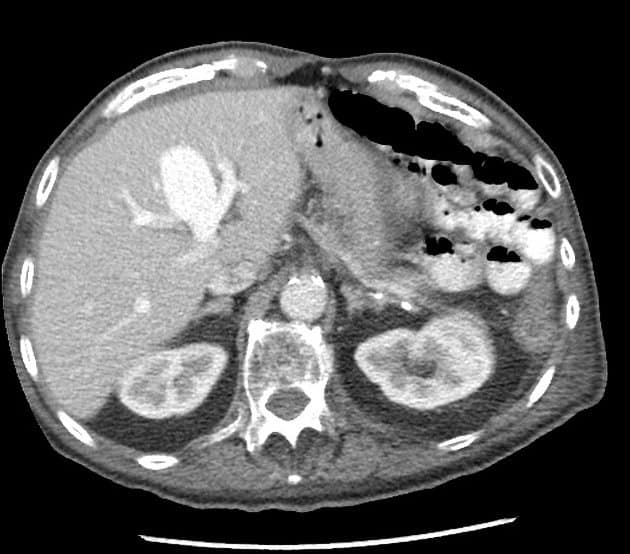

Phình TM cửa - Ảnh 4

Phình TM cửa

» Thông tin: Nam giới – 90 tuổi.

» Lâm sàng: Kiểm tra sức khỏe.